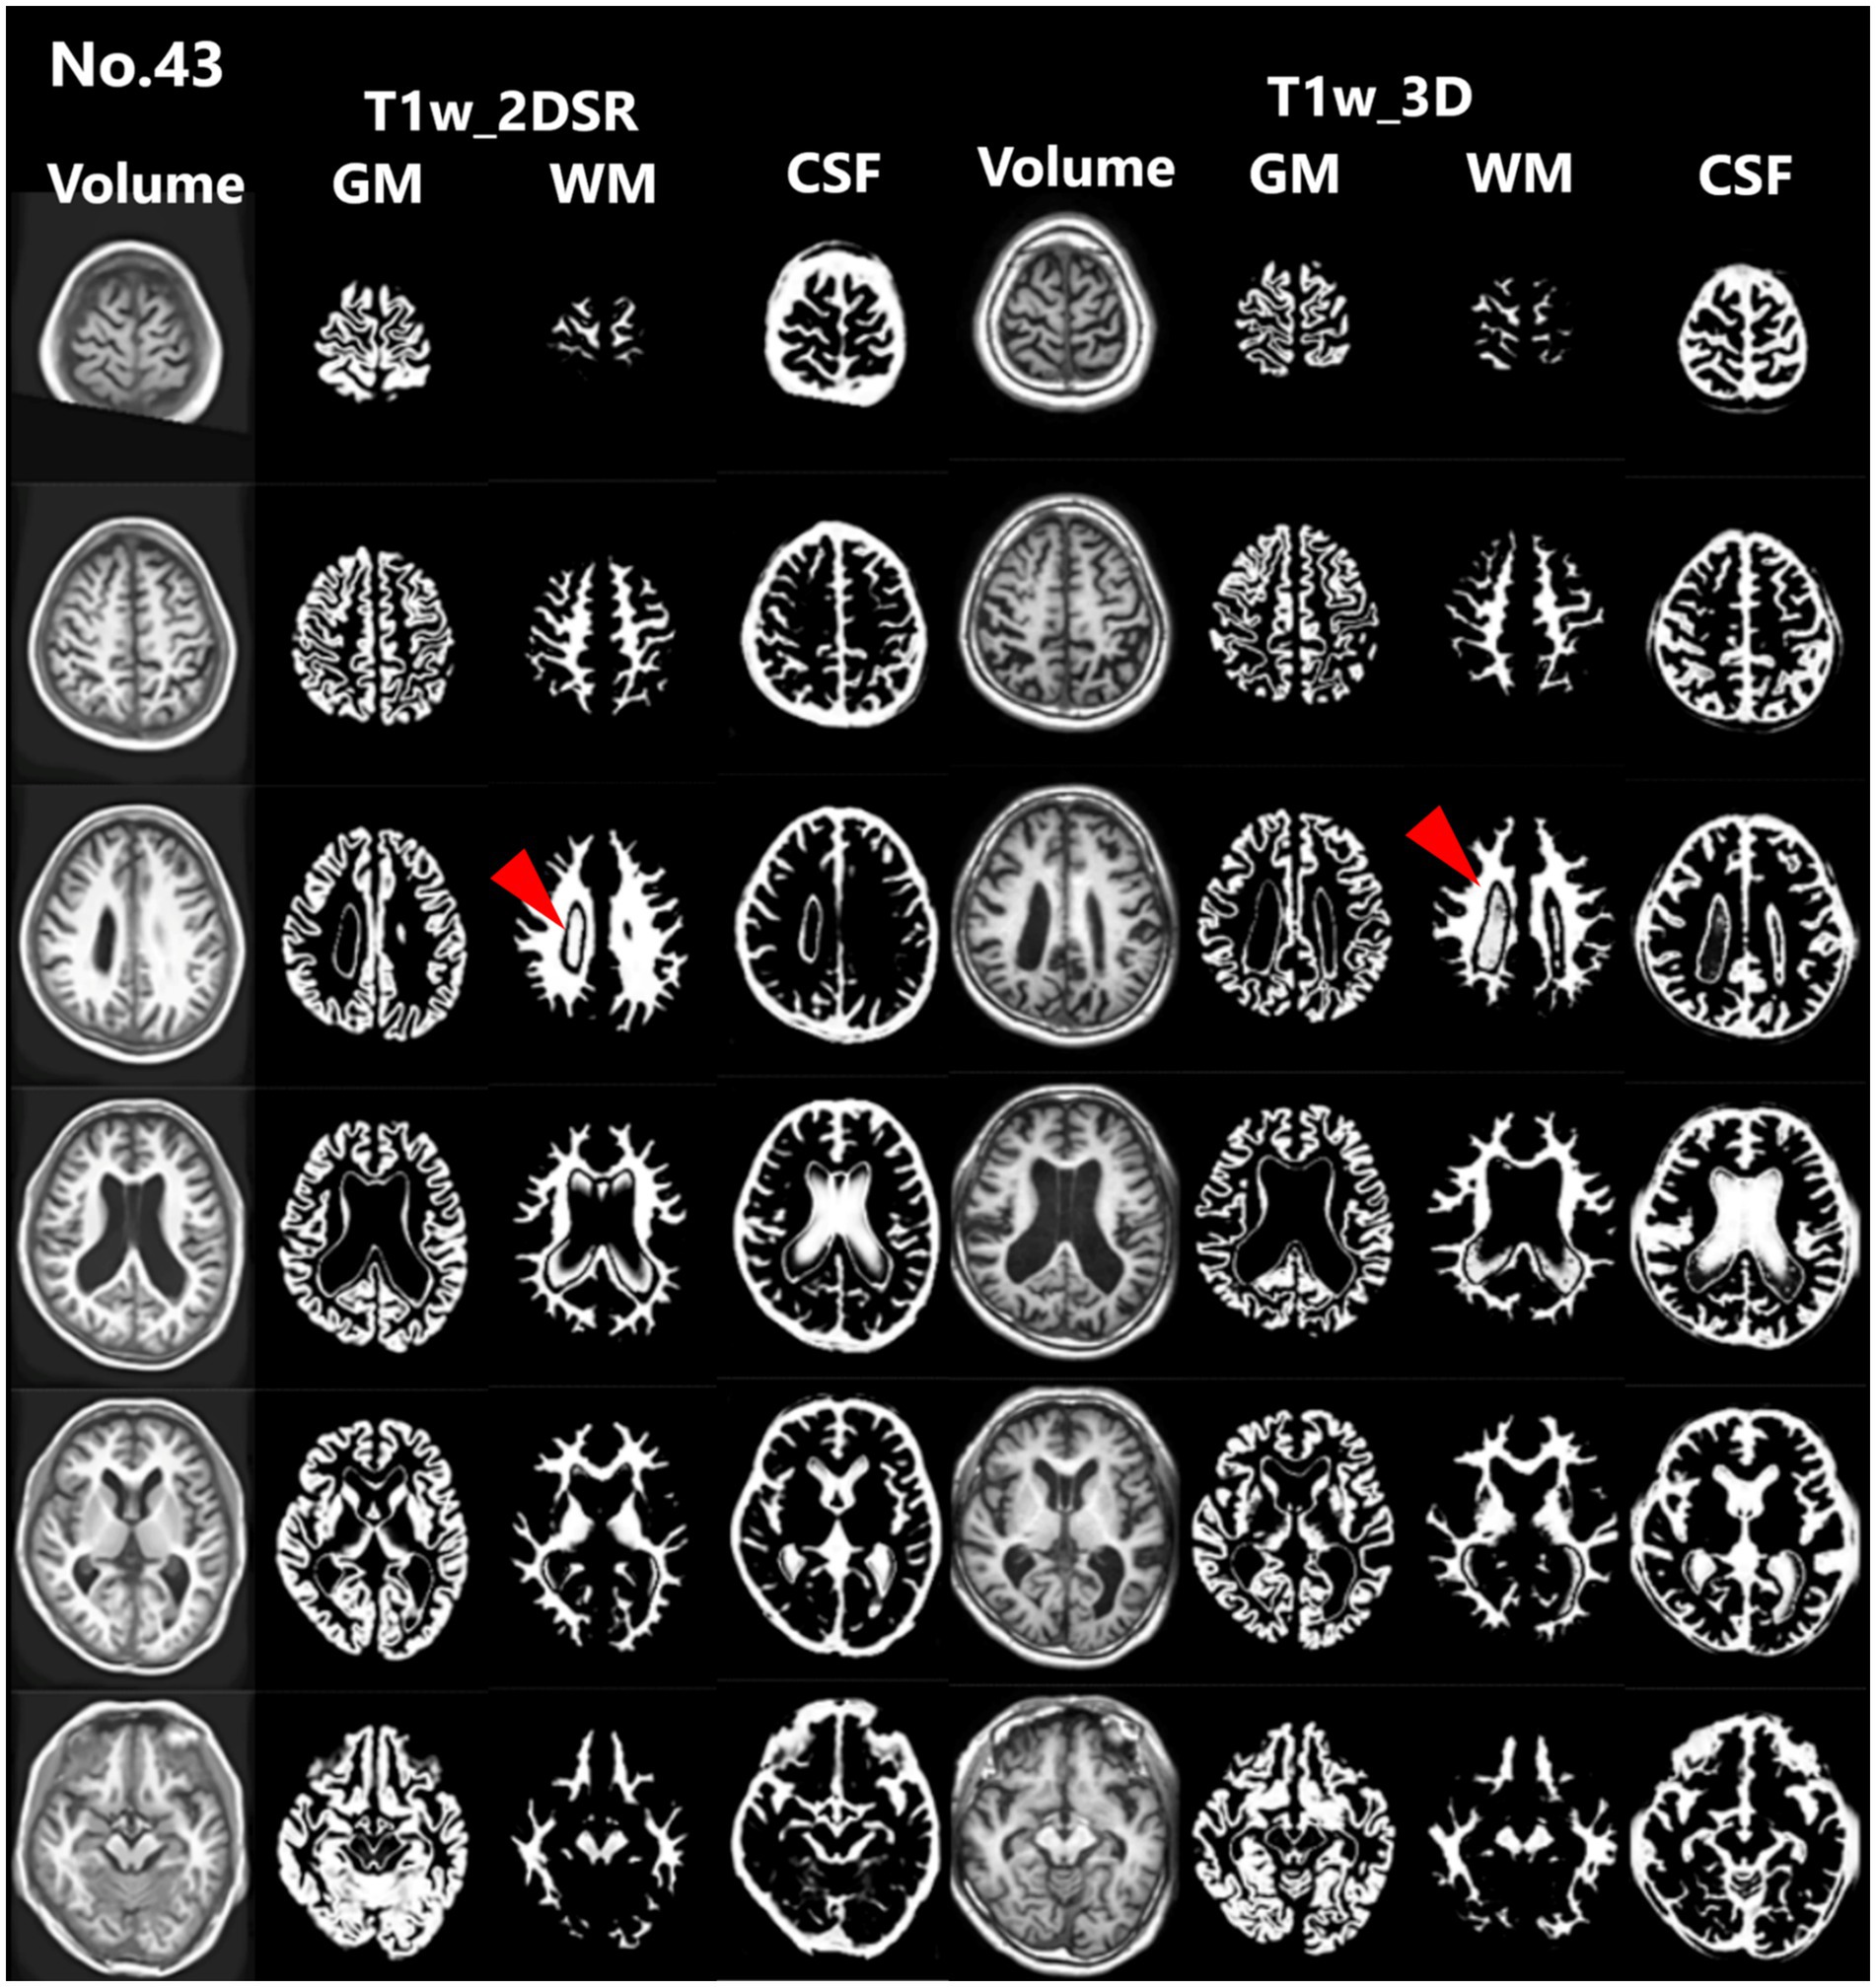

Seventy-five patients underwent MRI during the study period. Of these, 21 (28.0%) were male. The mean age was 83.5 years (range, 61–107 years). This cohort reflects the typical population undergoing dementia screening in Japan. For all cases, 3D volume data (T1w_2DSR) were successfully generated from T1w_2D using SynthSR. The generated T1w_2DSR did not reconstruct the parietal CSF region because it was not imaged in the original T1w_2D. Each output image was independently reviewed by two neurosurgeons. Cases with obvious motion artifacts and disrupted WM and GM segmentation in the control T1w_3D images were excluded from the analysis. Among the excluded cases, four (Cases 22, 26, 43 and 63) had showed segmentation errors involving the ventricles and GM due to brain atrophy (Figure 3), five (Cases 7, 11, 12, 69 and 72) showed segmentation failure caused by motion artifacts; and two (Cases 15 and 39) had structural brain lesions due to stroke (Figure 4). A total of 64 cases were analyzed after excluding 11 cases. After VSRAD analysis, four scores and three volumes were calculated. For these evaluated indices, normality was not met in most cases (Shapiro–Wilk test, p < 0.05), and thus non-parametric comparisons were adopted.

Figure 3. Representative excluded cases of atrophy. In Case no. 43, severe brain atrophy led to segmentation failure in both the standard and proposed methods, with portions of the ventricles erroneously classified as white matter (red arrowheads).